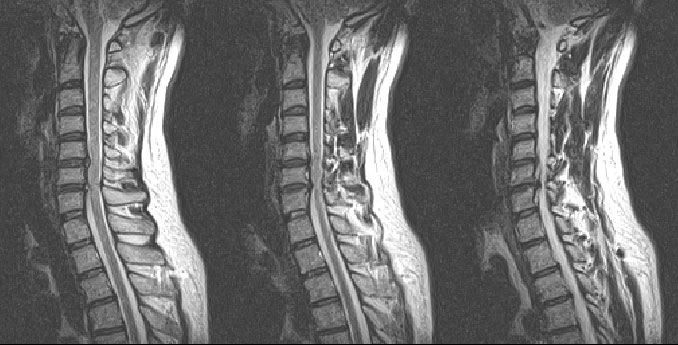

mri ȸԲ ð 迵ռԼ ȣ ְ Ͻ ̶ ϼ̽ϴ. Ͻð ȣ ǰ ͵帮. /Ű// / 169 / 83 / 33 ˰Ե ͳ ˻ڷ õ ش 1C.Ż, 1C., 6C.ڸ 6C. κ 6C.ھ Ḳ ()ũ( ߰Ż) Ը ũ(߰Ż)ġ, , Ḳ ġ Ǵ ġ ϰ Ѱ ()ũ ̿ , , , 2009 2 ߺ ũ ܹް Űֻ ġϿ 4 ٰ 11 Ͽ ݱ ӵ 2 ʹߺ mriԴϴ. |